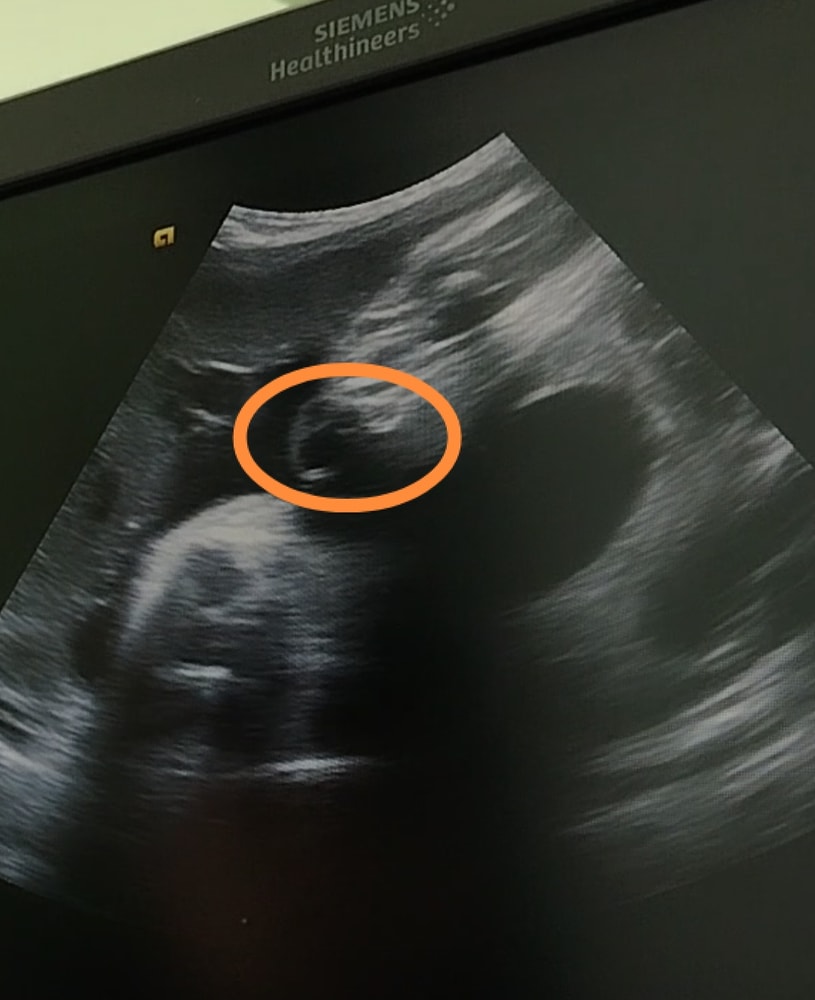

Затрудняюсь с категориейДевочки как думаете, у девочки могут так свисать из ягодиц половые губы🤔? На втором скрининге, на современном аппарате сказали 100% девочка, в 33 и 37 недель сказали что больше теперь на кукушата похожи, пол плохо видно, ещё пуповиной всё перекрыто. Как на Ваш взгляд девочка или мальчик?

Алёна Хаустова, а на этом стоп кадре🤗? Это могут быть тоже половые губы🙂

Ирина Лапина, похоже на губы,просто изображение на узи плывёт, сложно чётко зафиксировать)

Эльза, а на этом стоп кадре вроде как писюн вверх к мочевому задран, или это такие половые губы🤔?